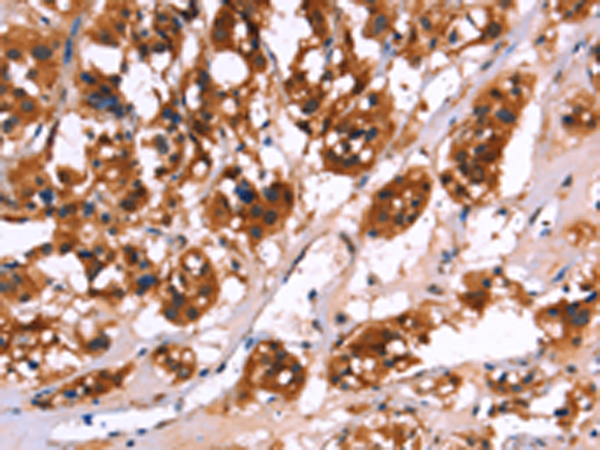

分类: 科研抗体货号: P08132别名: p67; SIGLEC3; SIGLEC-3应用: WB,IHC反应种属: Human, Mouse